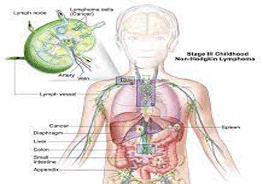

Other common cancers in children include lymphoma (cancer involving the lymph nodes), brain tumors, bone tumors, tumors of kidney or adrenal gland, soft tissue sarcomas, tumors involving the eyes, liver etc.

- Prolonged fever for more than 2-3 weeks which is not controlled with routine medications and no definite cause of fever is detected.

- Painless swelling in the neck or axilla, increasing in size or associated with fever, cough, weight loss etc.

- Bluish or black spots over body, bleeding from gums or nose.

- Early morning vomiting or persistent headache, changes in eye, abnormal gait

- Abdominal swelling

- Joint pains associated with fever and pallor

Symptoms are usually dependent on the type of cancer. These symptoms can occur in other diseases also, but a little bit of alertness on the parts of the parents and the pediatricians is never a waste.